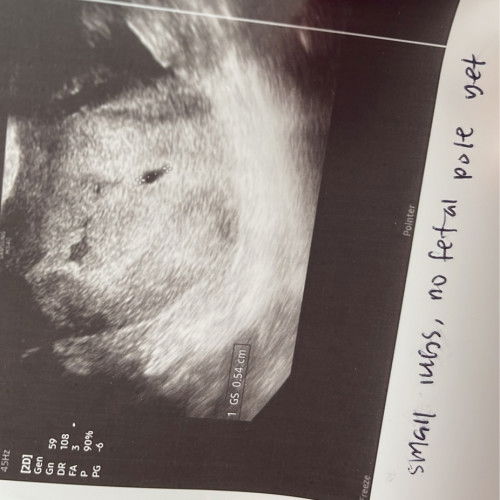

kantung tak cantik

saya perlukan advice. tadi pergi scan baby dalam kandungan dah 5 weeks & doctor cakap kantung tak berapa cantik. anyone ada pengalaman tak pasal ni & baby survive tak? saya risau hm #Needadvice